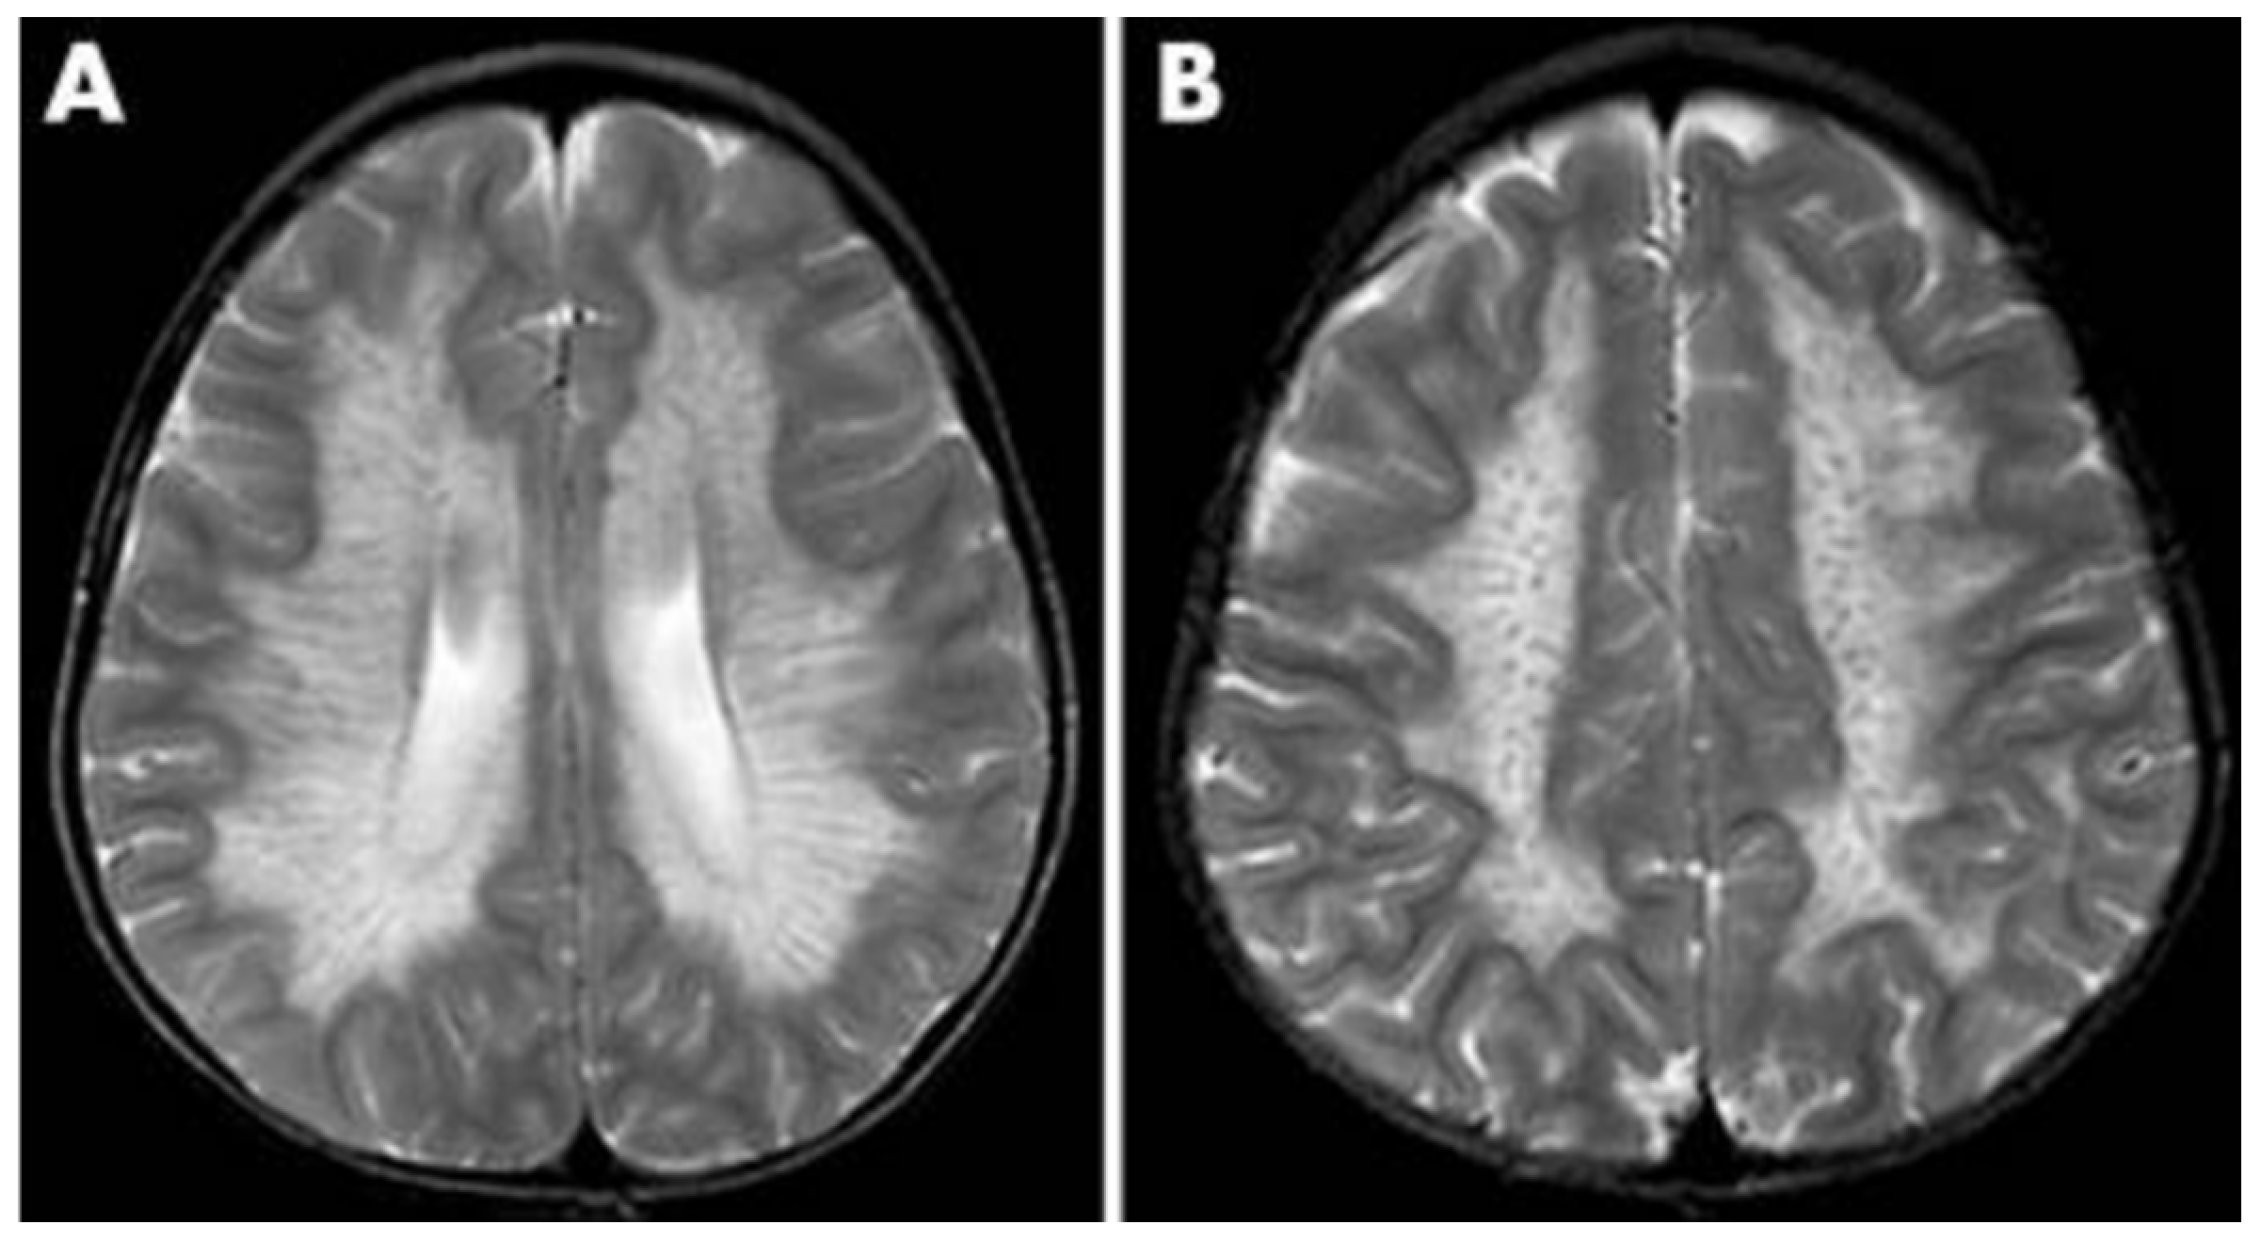

Additionally, as a demyelinating condition, brain demyelination will be present on MRI along with abnormalities of nerve conduction [32,33]. The central and periventricular white matter are often impacted first with the subcortical structures being affected as the disease progresses. In extreme cases, projection fibers are also impacted resulting in a “tigroid pattern” and “leopard skin” pattern (Figure 3) [34,35]. One study found that nearly all patients with metachromatic leukodystrophy displayed splenial corpus callosum demyelination [36]. Additionally, MRI demonstrates T2-weighted FLAIR symmetric, confluent hyperintense areas of the periventricular white matter. Hyperintense areas are visible on T1-weighted images as metachromatic leukodystrophy is a demyelinating disorder [37].

Figure 3. MRI findings found in metachromatic leukodystrophy. (A) Hypointense radial stripes resembling tiger skin. (B) Hypointense dots resembling leopard skin [35].